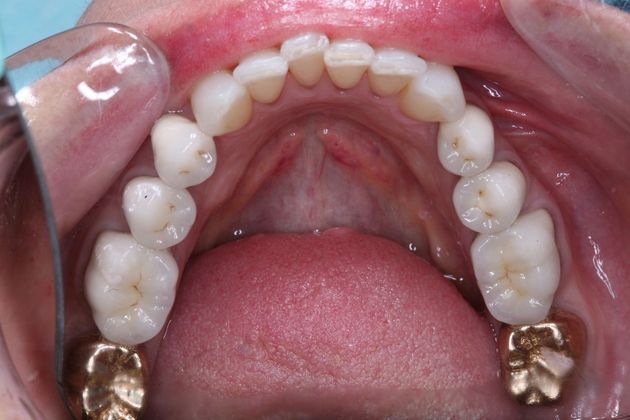

Procedures; TMJ CAT scan, TMJ deprogramming, whitening, sedation dentistry, reconstruction of all the back and upper front teeth with porcelain crowns, bite guard therapy. This foster care provider wanted to be free of the pain in her jaw joints. She had a lifelong history of grinding, many of her back teeth were breaking down and her bite was off. Her treatment was performed in sections to spread out the cost. She and her husband were so pleased with the result!